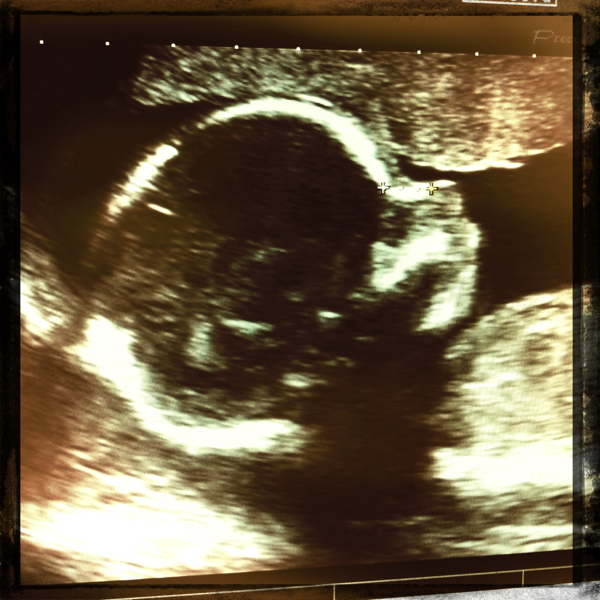

Due on 08/31/11

Gaia